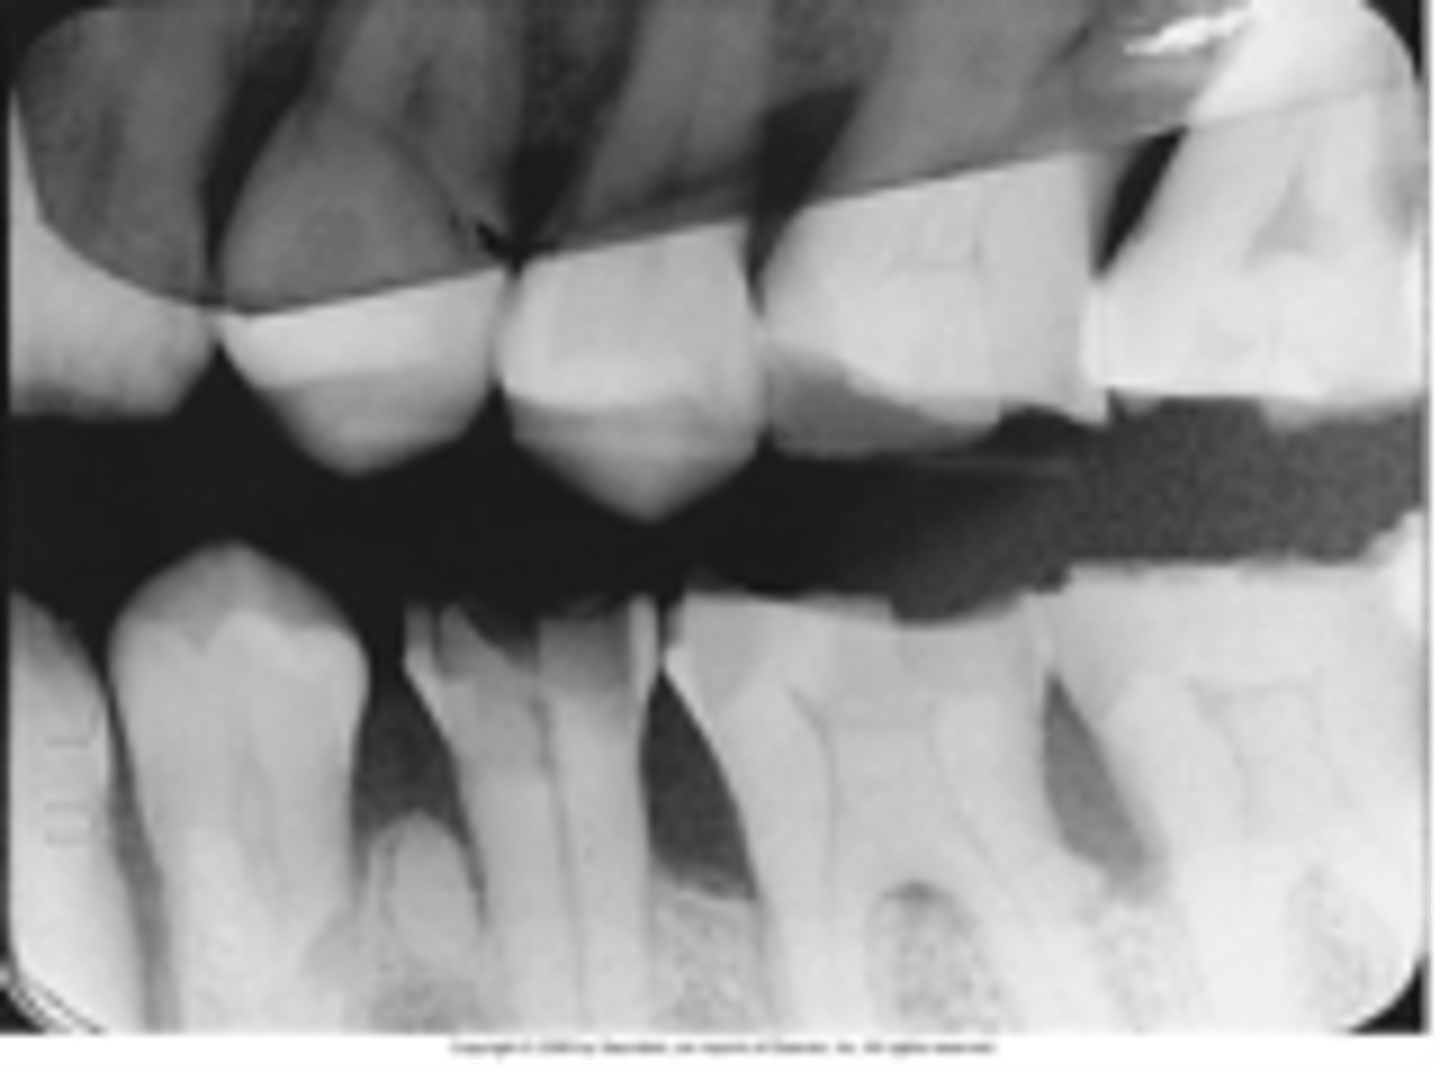

Overlapped interproximal contacts

Result from incorrect horizontal angulation; be sure to direct the x-ray beam through the interproximal regions.

<p>Result from incorrect horizontal angulation; be sure to direct the x-ray beam through the interproximal regions.</p>